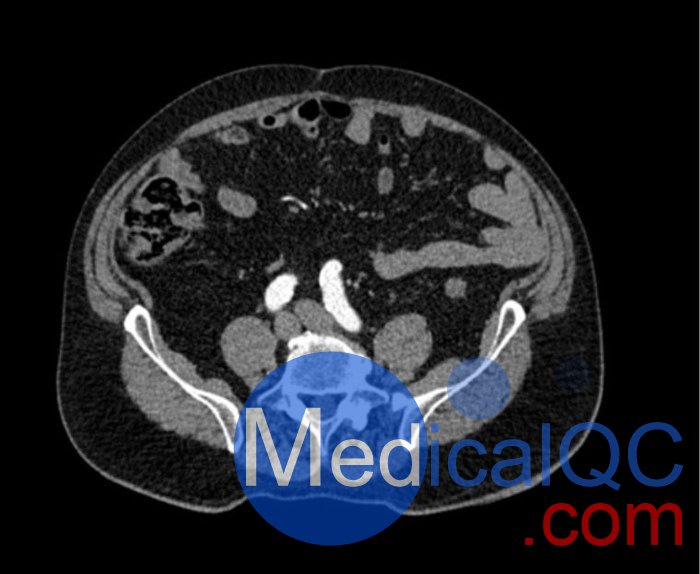

WEK53-05腹部模體,WEK53-05動脈瘤腹部模體,WEK53-05 CT血管造影模型模擬了動脈期的造影劑增強腹部。它覆蓋第一腰椎至第四骶椎。它有一個腎下腹主動脈瘤。

真實模擬脈管系統、骨骼和軟組織,包括肝臟、胰腺、脾臟、腎上腺、腎臟、胃、小腸和結腸。

肝硬化,膽囊切除術,下腔靜脈濾器,腎囊腫,腎結石,淋巴結。